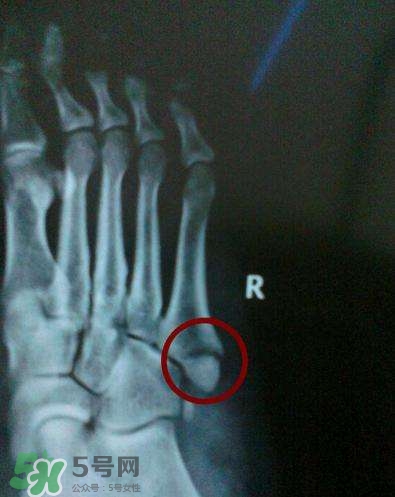

骨裂是骨折的一種,臨床上嚴(yán)格來說沒有骨裂這個(gè)說法, 骨裂只是普通的說法,是骨折的輕微狀態(tài),也就是骨頭裂開了,但是沒有移位,骨頭之間對(duì)位對(duì)線都是好的,所以一般不需要復(fù)位,只需要固定就可以,而骨折是一大類,包括沒有移位的骨折,也包括有移位的骨折。

骨裂的康復(fù)時(shí)間是多長(zhǎng)

一般骨裂分為移位骨裂和無移位骨裂、關(guān)節(jié)內(nèi)骨裂和關(guān)節(jié)外骨裂,一般骨裂4-6周軟骨愈合,3月以上骨性愈合,不愈合的很少見,但是畸形愈合的較多見。但是這也不是絕對(duì)的,需要看骨裂的具體的部位損傷的程度。